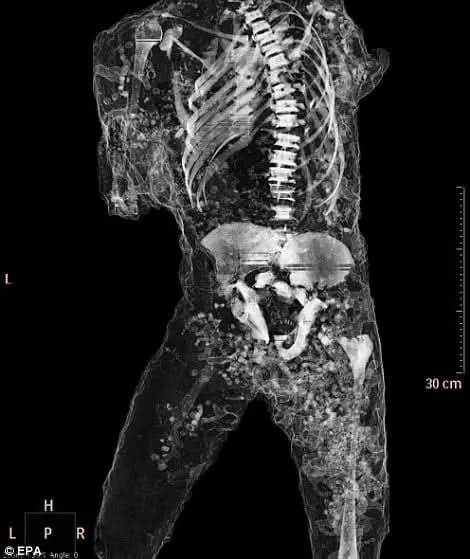

Recent CT scans of the Pompeii casts have opened a new window into this ancient tragedy, offering a clearer, more intimate understanding of the lives—and deaths—of its victims.

Thanks to modern CT imaging, researchers can now examine the interior of these casts without damaging them. The scans have revealed:

1. Intact skeletal remains

The casts often contain skulls, rib cages, teeth, and long bones still in their original anatomical positions. The plaster formed around them like a second skin.

3. The moment of death

The positioning of bones inside the cast often confirms the outward posture. Some victims died instantly from thermal shock; others collapsed while attempting to shield loved ones.

4. Objects preserved with the body

CT scans also detect items that would otherwise remain unseen:

-

jewelry

hairpins

belts and buckles

coins

tools

These personal objects create a more intimate portrait of the people who lived—and died—in Pompeii.